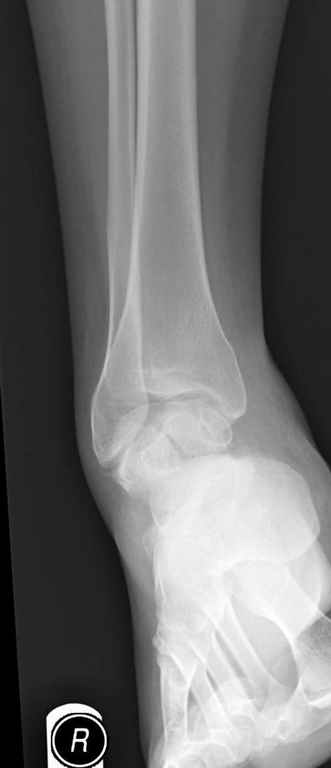

Уважаемые участники русского Ортофорума, поздравляю всех со всеми прошедшими праздниками: Новым годом, Рождеством, Hanukkah, Kwanzaa, желаю участникам всего наилучшего и здоровья.Повреждение таранной кости.Больной 81г автоавария, повреждение таранной кости, здесь снимки. Какие рекомендации?Djoldas Kuldjanov, MDDepartment of Orthopedic SurgerySt. Louis University Medical Center

Вдогонку по поводу перелома таранной кости, больная 81, не страдает диабетом, перелом закрытый, в первый же день поступления ограничились временным наружным фиксатором (как на снимке).

Планировалась открытая фиксация после спадения отека, но больная пожелала лечиться по месту жительству в другом штате..

За пару недель насчитал 5 больных с переломом таранной кости, из них двое с двусторонним повреждением.

Из-за отека на стопе тактика лечения у всех была

одинаковая: временная наружная фиксация до спадения отека, при изолированных переломах они выписывались домой и через дней 7 госпитализировались на оперативное лечение.

Примеры на снимке...